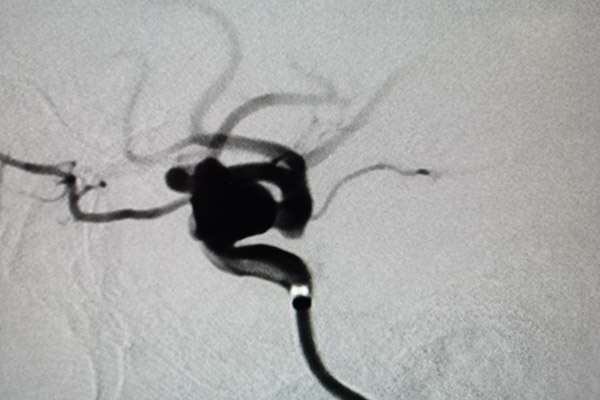

確定手術方案后,由吳剛副主任醫師主刀對患者進行血流導向裝置置入+彈簧圈栓塞術治療,經精確測量,選擇了一枚與載瘤動脈匹配良好的血流導向裝置,手術中裝置一次到位并且順利釋放。術中造影復查發現病變頸動脈內血流受血流導向裝置引導基本恢復正常流徑,整個手術過程十分順利,患者獲得了理想的血管重建。